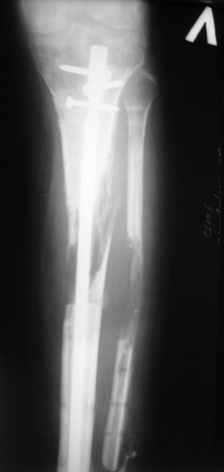

Больному выполнена резекция малоберцовой кости, ВХО раны, сближение отломков. Резекция м\б через отдельный разрез. После ВХО компрессия в аппарате, края раны сближены наводящими швами (без натяжения).

В случае гладкого заживления раны, при условии положительного решения вопроса с металлом, планируем перемонтаж аппарата Илизарова, дополнительную резекцию дистального отломка, выведение полокости голеностопного сустава в правильное положение (см. боковую Р-грамму), одномоментно остеотомия большеберцовой кости. После восстановления длинны голени, по всей видимости, артродез голеностопного сустава.

Рентгенограммы прилагаются. Фото местного статуса выложу в ближайшее время.

Мы обычно не фиксируем малоберцовую кость. Просто стараемся сопоставить ее концы за счет хорошей репозиции. В представленном случае имеется некоторое смещение дистальных фрагментов кнаружи, и, как мне кажется, ротация их вместе со стопой кнутри (ротация хорошо заметна на прямом снимке по форме таранной кости и на боковом по соотношению отломков малоберцовой). Если это действительно так, то это несложно сейчас постепенно устранить в аппарате. И тогда концы малоберцовой кости будут находиться поближе друг к другу.